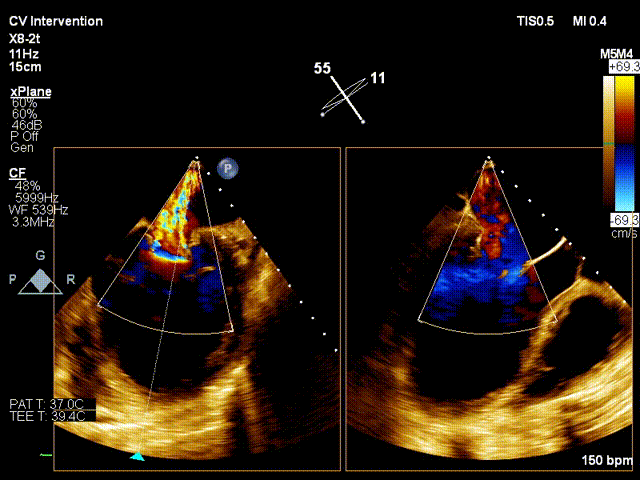

考虑患者残余反流仍偏高,经团队评估后,遂植入第二个夹子。术后即刻(植入第二个夹子)TEE示:二尖瓣反流降低至微量,二尖瓣压差1mmHg;测定左房压力:19/16/14mmHg,手术成功。患者术后即刻麻醉清醒,血压维持在110/60mmHg, 胸闷,呼吸困难症状明显缓解。

Final